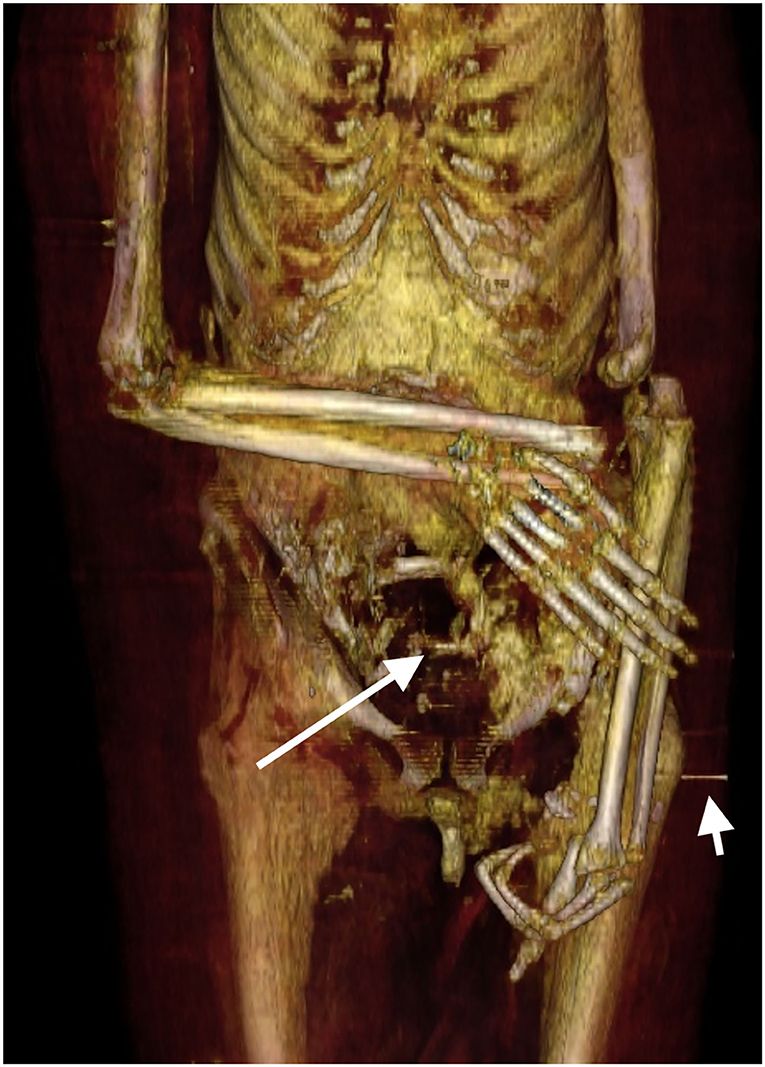

O que eles descobriram foram vários ferimentos post-mortem que provavelmente foram infligidos ao corpo por ladrões de túmulos.

Esse dano foi “reparado com amor” pelos padres mortuários da 21ª Dinastia, cerca de 400 anos após a morte de Amenhotep. Eles usaram uma faixa de linho tratada com resina para recolocar a cabeça e o pescoço juntos.

Os pesquisadores também encontraram cerca de 30 amuletos escondidos entre as bandagens de Amenhotep.

O fato de eles ainda estarem lá mesmo depois de seu enterro provavelmente desmente a teoria de longa data de que os sacerdotes de dinastias posteriores reutilizariam os ornamentos nos ritos fúnebres de seus faraós.